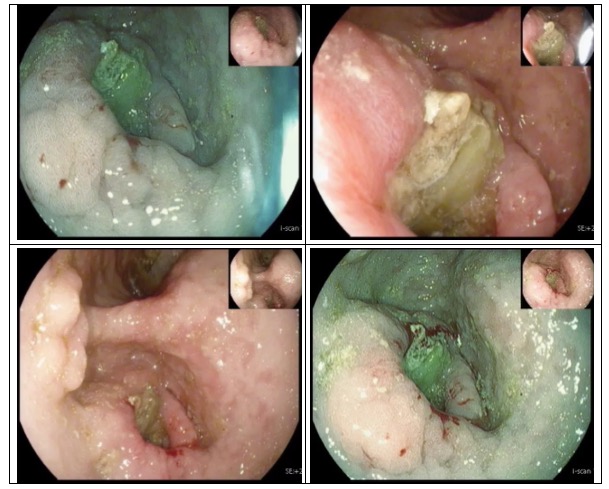

走進(jìn)6診,是一位71歲急診檢查的患者,患者胃內(nèi)大量食物潴留,視野欠清,胃竇及幽門見一不規(guī)則環(huán)形腫物,腫物表面污穢不平,管腔狹窄,內(nèi)鏡無法通過,胃竇前壁見約1.5*1.2cm丘狀隆起,中央凹陷。內(nèi)鏡醫(yī)生陳大夫給予病理活檢,待病理結(jié)果出來行進(jìn)一步治療。

走進(jìn)7診,是一位76歲懷疑胃癌伴幽門不全梗阻的患者,同樣在胃竇、幽門處見環(huán)形不規(guī)則隆起腫物致幽門狹窄,鏡身無法通過。

一早上,兩個(gè)胃癌的故事并不是騙人的,是我們每天都在經(jīng)歷的。不禁感嘆,如果早點(diǎn)發(fā)現(xiàn)內(nèi)鏡下處理,不僅創(chuàng)傷小而且恢復(fù)快,還是要呼吁大家早癌的篩查太重要了!